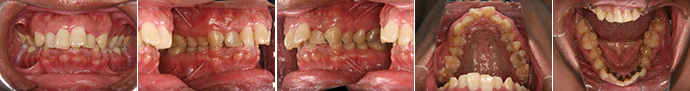

| 主訴 | 上顎前歯のデコボコ、下顎犬歯の突出が気になる |

| 年齢・性別 | 26歳 / 女性 |

| 治療方針 | 上顎前歯部に叢生と下顎犬歯の近心傾斜があるⅠ級叢生。口元の突出感の改善を希望しているため小臼歯の抜歯を行う |

| 抜歯部位 | 小臼歯4本抜歯 |

| 使用装置 | マルチブラケット装置 |

| 治療期間 | 28か月 |

| リテーナー | 上顎インビジブル、下顎インビジブル |

| 費用 | 825,000円(税別) |